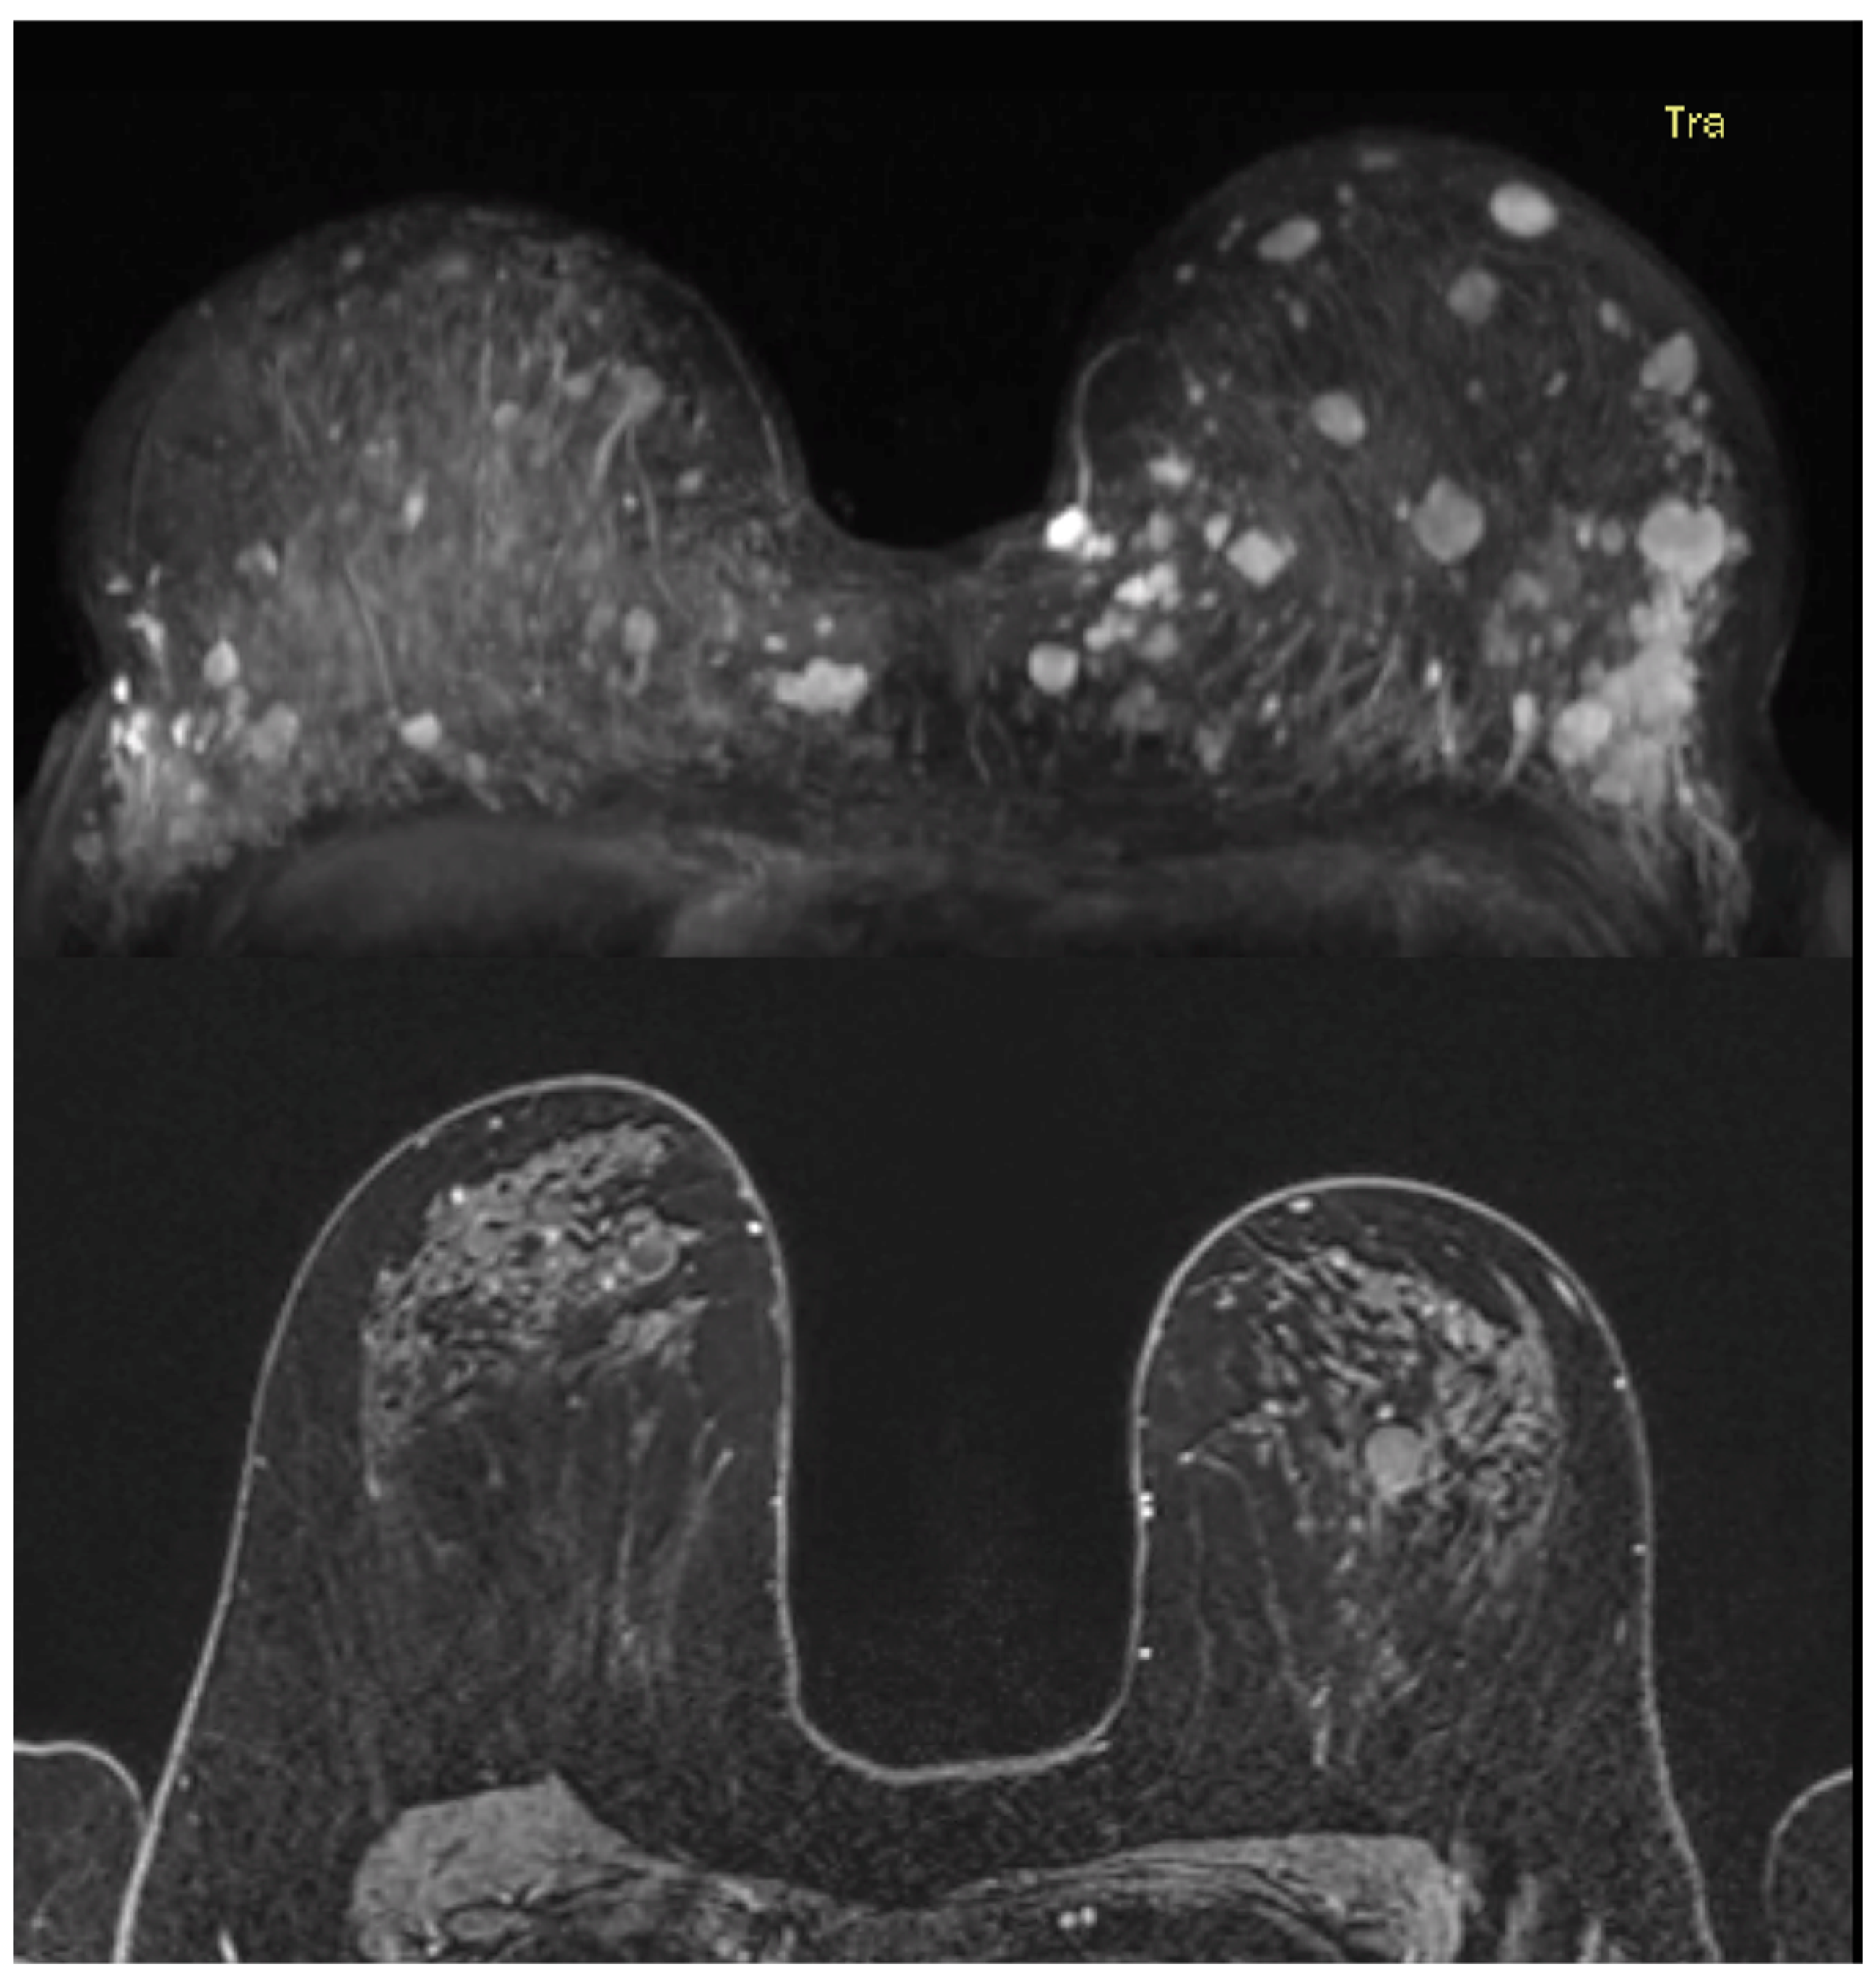

3.4. Imaging Features and Corresponding Pathology Outcome of Benign Breast Lesions

In total, 89 distinct pathologically confirmed benign breast lesions were diagnosed within 23 women (35%), with a median age of 38 years at first diagnosis (range, 15–61 years). Imaging examinations for 31 benign breast lesions in 16 women were available for re-evaluation. In five of these cases, multiple (>20 per side) well-defined benign breast lesions were radiologically identified during the re-evaluation of the imaging examinations (Figure 7). For these women, only the three most significant lesions were described following the BI-RADS lexicon.

Figure 7.

MRI examinations of two women with multiple benign breast lesions in both breasts.